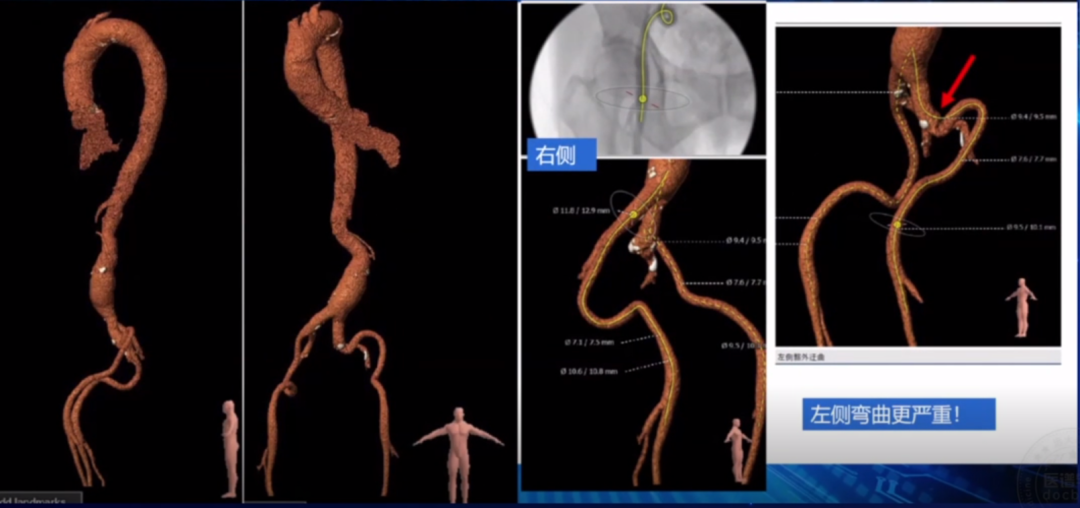

CT评估:

瓣环周长83.5mm,平均直径26.6mm,左室流出道周长85.5mm,平均直径27.2mm,升主动脉直径37.3mm,STJ直径33.3mm,左冠高度12.7mm,右冠高度14.7mm。

瓣环结构:瓣环底部有钙化,延伸至流出道,为功能性二叶瓣;右无及左无交界有明显钙化融合,右无更严重,角度48°,钙化积分815.9mm。

外周血管入路:腹主动脉有瘤样扩张,右侧有迂曲,左侧迂曲折角。